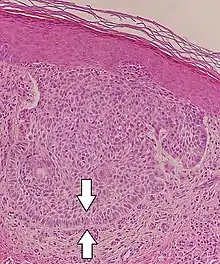

Nodular basal-cell carcinoma (also known as "classic basal-cell carcinoma") accounts for between 50% and 80% of all BCC.[2] It most commonly occurs on the sun-exposed areas of the head and neck.[2] Histopathology shows aggregates of basaloid cells with well-defined borders, showing a peripheral palisading of cells and one or more typical clefts.[17] Such clefts are caused by shrinkage of mucin during tissue fixation and staining.[18] Central necrosis with eosinophilic, granular features may be also present, as well as mucin. The heavy aggregates of mucin determine a cystic structure. Calcification may be also present, especially in long-standing lesions.[17] Mitotic activity is usually not so evident, but a high mitotic rate may be present in more aggressive lesions.[17] Adenoidal BCC can be classified as a variant of NBCC, characterized by basaloid cells with a reticulated configuration extending into the dermis.[17]

Cleft.